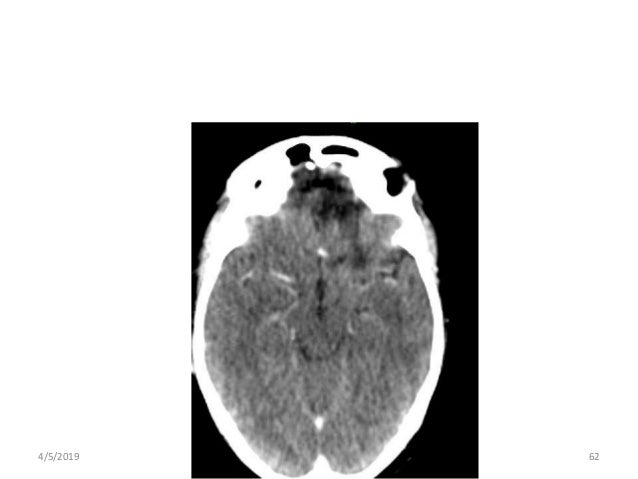

Pituitary tumor case study image This image shows pituitary tumor case study.

Their etiology is largely unknown. Pituitary tumor powerpoint table 3. At necropsy, a pituitary tumor measuring 25 × 18 × 15 mm was found. We conducted a population-based case-control study of potential risk factors for pituitary tumors in southeast england. Our case the lesion was extended in the suprasellar region with a curvilinear calcification on pre-operative ct imaging and the tumor was removed transsphenoidally.